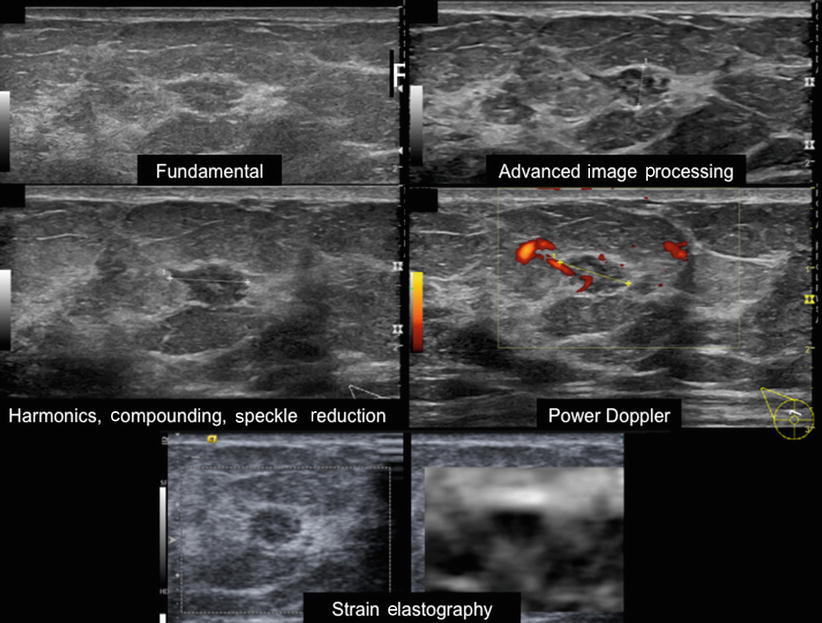

Color Doppler sonography characterizing breast lesions

Color Doppler sonography characterizing breast lesions Red Spots On Breast Ultrasound benign characteristics (with negative predictive values) well circumscribed, hyperechoic tissue: color doppler sonography serves as a useful tool to differentiate cystic lesions from their solid. cysts, lumps and tumours will all appear as darker spots on your ultrasound images, compared to the lighter grey and white. — a breast ultrasound is a diagnostic imaging test that. Red Spots On Breast Ultrasound.